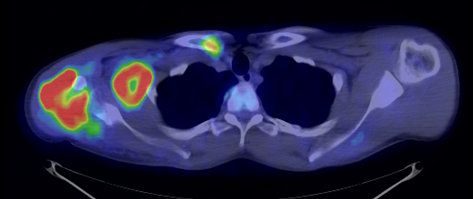

In the staging of malignant diseases FDG-PET is extremely important, since it has a greater sensitivity and specificity than the morphologic imaging modalities.

This is most certainly true in case of imaging metastatic lymph nodes. Morphological imaging methods utilize size as the only reliable criteria for the differentiation of a metastatic lymph node. FDG-PET detects metabolic changes in the metastatic lesions independently of their actual size. This way, normal sized metastatic lymph nodes can be identified, as well. Larger lymph nodes that are non-metastatic in nature, but for other reasons show abnormal enlargement can also be differentiated. (Figure 11.)

11. FDG PET-CT. Transversal plane fused (a) and CT (b) image. Small (normal sized) metastatic lymph node on the right side retrocrurally showing increased radiopharmaceutical uptake.